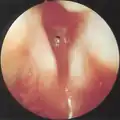

Subglottic stenosis is graded according to the Cotton-Myer classification system from one to four based on the severity of the blockage. Grade 1 is up to 50% obstruction, Grade 2 is 50-70% obstruction, Grade 3 is 70-99% obstruction, and Grade 4 is with no visible lumen.[5]